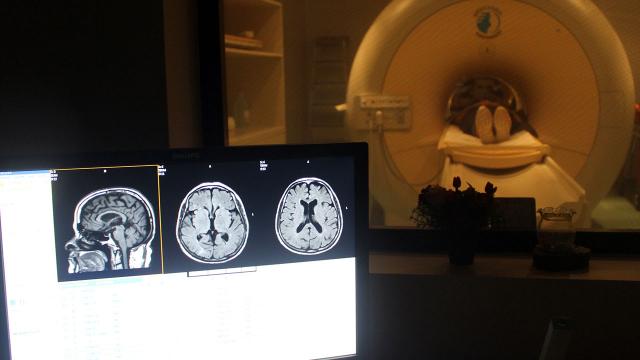

BBC’de yer alan habere göre, bilimsel dergi Nature’da yayımlanan araştırma kapsamında, bilim insanları COVID-19 enfeksiyonu geçiren kişilere hastalıktan önce ve sonra manyetik rezonans görüntüleme (MRI) yöntemiyle taramalar yaptı.

Bilim insanları yüzde 96’sı hafif COVID-19 semptomları taşımış 401 kişinin beyinlerini hastalıklarından yaklaşık 4,5 ay sonra yeniden görüntüledi. Araştırma kapsamında hastalık geçirmeyen 384 kişi de incelendi.

Araştırmanın sonucunda, enfekte olmuş katılımcılarda genel beyin boyutunun yüzde 0,2 ile yüzde 2 arasında küçüldüğü gözlemlendi.

Önemli farklılıklar bulunan taramalarda ayrıca beynin koku ve hafıza ile ilgili bölümlerinde gri maddede kayıpların yaşandığı görüldü.